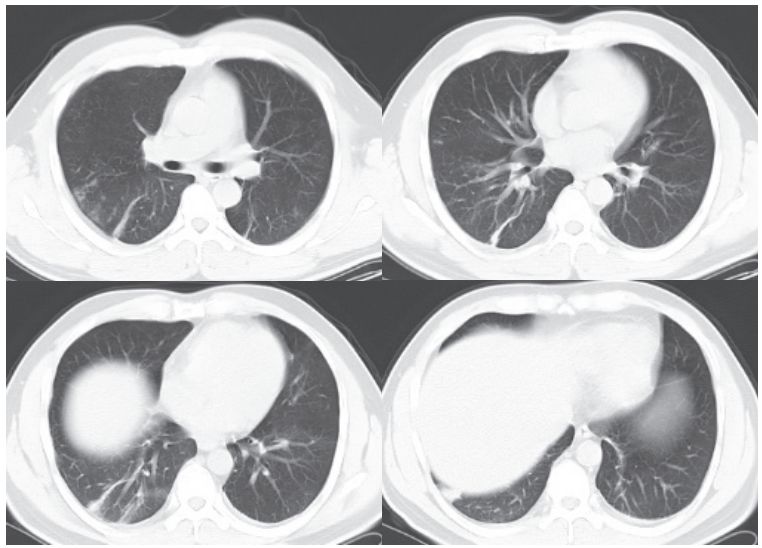

二、进展期征象

新冠肺炎大多数病例进展迅速,复查 CT 影像发生明显变化。

表现为病灶数目明显增多,范围明显扩大,密度增高,病灶分布由外周向中央推进。

根据既往 SARS 病理学机制,提示为肺泡腔内聚集大量细胞渗出液、间质内血管扩张渗出;肺泡连通起来形成融合态势(图 2-11)。

图 2-11 病灶数目增多、范围扩大 (A-D)